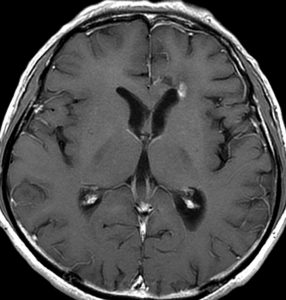

高齢者に発生したグリオーマです。左はガドリニウム増強MRIといいます。腫瘍の周囲が白く縁取られるように見えます。でも,右側のT2強調画像では,白く滲む部分が周囲に広がっています。

グレード3(かつての退形成性星細胞腫)かグレード4(膠芽腫),おそらく膠芽腫と「予想」できる画像です。確実ではないのですが,この予想は治療計画の上で重要なものです。